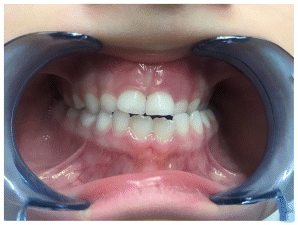

Case 4

The patient presented in early mixed dentition with a complete anterior crossbite associated with a bilateral posterior crossbite, resulting in a functional mandibular shift and lower dental midline deviation (Figures 27–34) (Table 7). Extraoral examination revealed a flat facial profile with a tendency toward convexity, a long facial pattern, and mild facial asymmetry, consistent with a functional component superimposed on an underlying skeletal Class III tendency. The treatment protocol involved the use of an AMCOP TC appliance, designed to address the transverse maxillary deficiency and eliminate the functional shift. The appliance allowed progressive transverse development of the maxillary arch, promoting spontaneous mandibular repositioning and restoration of a more physiologic maxillomandibular relationship during growth. Following active treatment, a complete correction of both anterior and posterior crossbite was achieved. Transverse arch coordination was obtained, with elimination of the unilateral posterior crossbite and resolution of the functional mandibular deviation. The occlusion was stabilized in a dental Class I relationship, with normalization of overjet and overbite and centering of the lower dental midline relative to the maxillary midline. From a sagittal perspective, the correction of the functional shift contributed to an improvement in the intermaxillary relationship, with favorable dentoalveolar adaptation and reduction of compensatory incisor inclinations. Vertical relationships remained stable throughout treatment, maintaining a normodivergent growth pattern. Extraoral assessment after treatment showed an improvement in facial balance and symmetry, with a more harmonious sagittal profile compared to baseline. The correction of occlusal relationships allowed a more stable mandibular posture, positively influencing soft tissue profile and facial proportions. The post-treatment lateral cephalogram (Table 8) and the clinical, occlusal, and photographic records clearly demonstrate total correction of the malocclusion, supporting the effectiveness of early interceptive treatment with AMCOP TC in patients with Class III malocclusion associated with transverse maxillary deficiency and functional mandibular displacement. Early orthopedic–orthodontic intervention appears to play a key role in restoring functional occlusion and guiding craniofacial development toward a more favorable pattern.